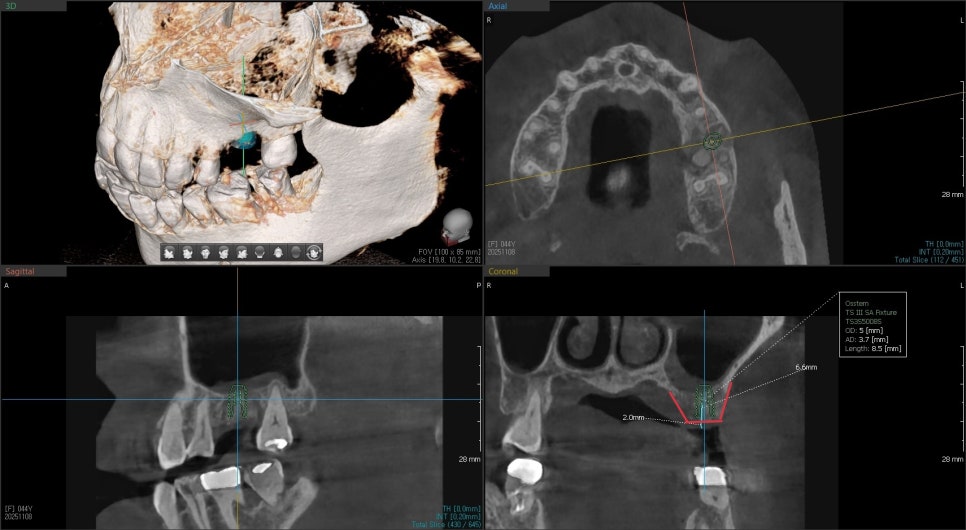

3D CT를 촬영해보니

가장 큰 뿌리 주변이 염증에 의해 뼈가 녹아있습니다

빨간선으로 표시된부분이 뼈로 채워져 있어야하지만

어둡게 보이는것은 염증으로 뼈가 녹았다는것을 보여줍니다.

이런경우 발치와 동시에 즉시 임플란트 수술이 가능은 하지만 추후 뼈가 어디까지 회복될지 예측이 어려웠기 때문에 발치를 했던 주변으로 치조골이식을 해서 볼륨을 유지시켜주는것을 발치와 보존술이라고 합니다

약 4개월후 빨간선으로 표시된것 처럼 주변 뼈들이 회복이 된것을 확인 후 임플란트 수술이 진행되었습니다.

이렇게 벽을 이루고 있는 뼈들이 녹아있는경우는 치조골 이식후 회복기간을 기다렸다 하는경우가 예측이 좀더 좋습니다